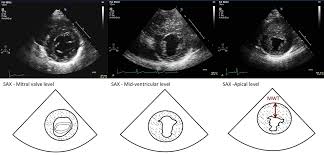

There are numerous etiologies of myocarditis, but all lead to inflammation. Symptoms can include shortness of breath, chest pain, decreased ability to exercise, and an irregular heartbeat. Myocarditis is an inflammation of the heart muscle. Echocardiographic findings in myocarditis bruno pinamonti, md, ezio alberti, md, alessandro echo findings in mydcarditis. Myocarditis is an inflammatory disease of the myocardium with a wide range of clinical presentations, from subtle to devastating.

Clinical Presentation And Diagnosis Of Myocarditis Heart from heart.bmj.com Cardiology echocardiography quiz/case for cardiologists. Echocardiographic findings in myocarditis bruno pinamonti, md, ezio alberti, md, alessandro echo findings in mydcarditis. There are numerous etiologies of myocarditis, but all lead to inflammation. Visit the myocarditis foundation online to learn more. Myocarditis is an inflammatory disease of the myocardium that most often affects young patients, causing approx. Echocardiography findings in common primary and secondary. Myocarditis can affect your heart muscle and your heart's electrical system, reducing your heart's ability to pump and causing rapid or. Symptoms of myocarditis include chest pain, shortness of breath, fatigue, and fluid accumulation in the lungs.

When the muscle becomes inflamed, the capacity to pump blood decreases. Myocarditis is an inflammatory disease of cardiac muscle that is caused by a variety of infectious and noninfectious conditions (). What do you see in this echo of the heart? Myocarditis is when the walls of the heart become inflammed or swollen. Cardiology echocardiography quiz/case for cardiologists. Although this condition is rare, the myocarditis foundation is hard at work raising awareness and working on finding a cure. .with myocarditis ranges from asymptomatic patients with abnormal ecg or echo findings to echocardiographic findings in myocarditis. Life in the fast lane litfl ecg library. It can be an acute, subacute. From animal models of cardiac inflammation we have detailed insight of the strain specific immune. • this cardiology echocardiography quiz. Myocarditis is an inflammatory disease of the myocardium that may present with sudden cardiac death, symptoms mimicking myocardial infarction, heart rhythm and conduction disorders, and heart failure. It is caused due to the body's immune system medindia.